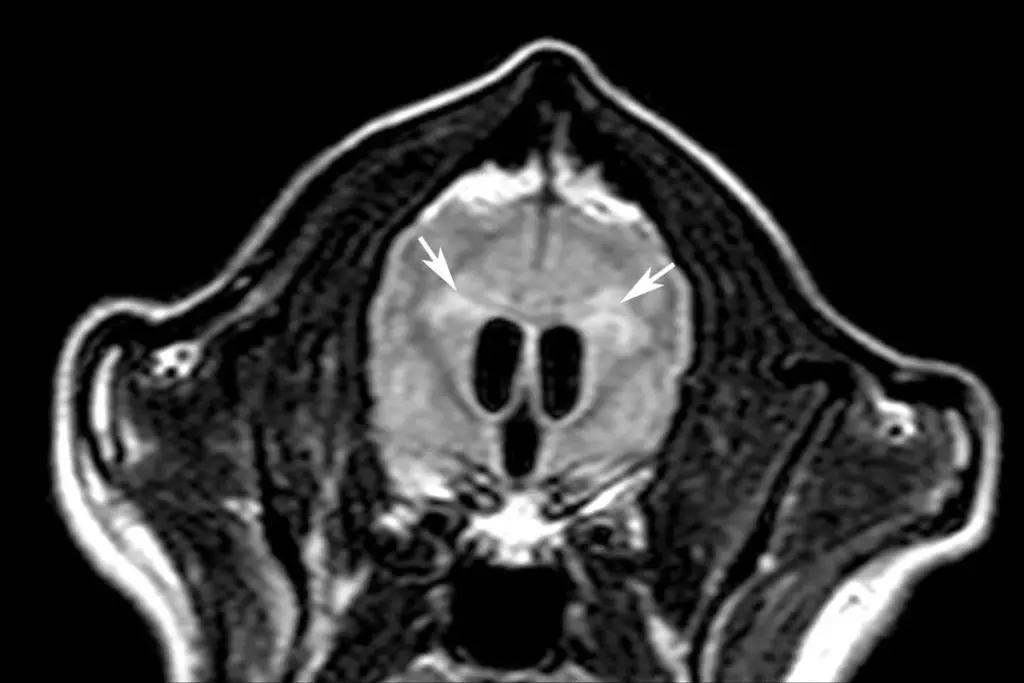

Neuroimaging Studies of Brain Ventricles

Neuroimaging is key in diagnosing hydrocephalus. We use ultrasound, CT, and MRI to see the brain’s ventricles. This helps us check their size and shape.

MRI is very sensitive and shows brain details without radiation. It’s good for looking at CSF pathways and finding blockages.

Endoscopic Third Ventriculostomy (ETV) is a surgery for hydrocephalus. It creates a new path for CSF to leave the brain. This is done by making a small hole in the third ventricle, helping CSF bypass any blockage.

ETV is an option for some patients with hydrocephalus, mainly those with obstructive hydrocephalus. The success of ETV depends on the patient’s age and the cause of hydrocephalus.